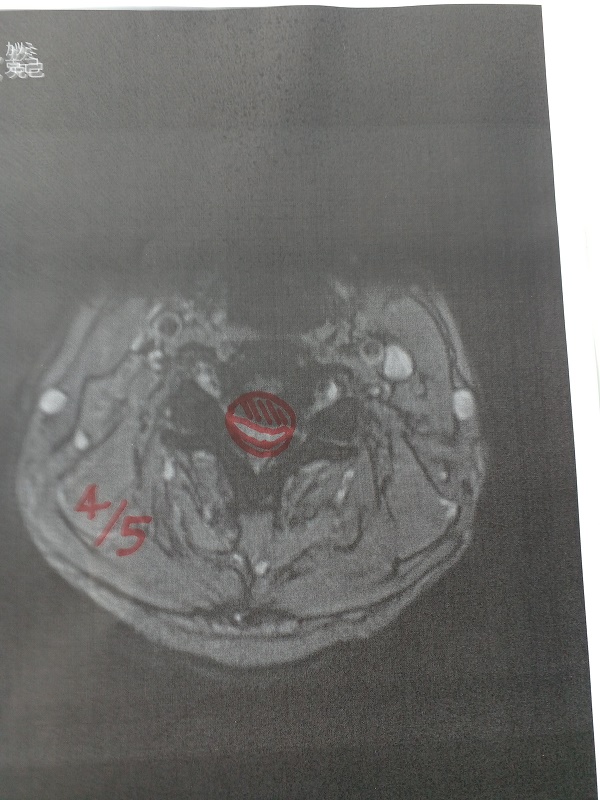

0.頚椎症は、進行せず安定。(働かなくなると首の筋肉が衰えて進行するかも)

写真11.頸椎の4番と5番の間の神経が、通常の半分まで狭められています。

写真12.頸椎の断面。赤の斜線部分が、半分つぶれています。